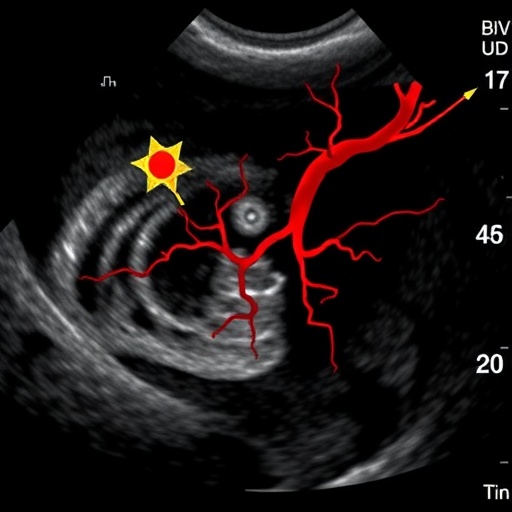

The study utilizes high-resolution ultrasonography, an imaging technique renowned for its precision in measuring arterial wall thickness. This modality allows researchers to visualize the arterial structure in great detail, offering insights that are crucial for risk stratification in diabetic patients. By measuring intima-media thickness (IMT), the study provides a reliable metric for assessing vascular health and potential atherosclerosis progression in this high-risk population.

Additionally, the study emphasizes the critical importance of regular screening and early intervention. Given the potential for collagen damage and arterial stiffening seen in diabetic patients, timely assessments using high-resolution ultrasonography could serve as invaluable tools for early detection of cardiovascular issues. This proactive approach could help avert severe complications, thus improving the quality of life for those living with diabetes.